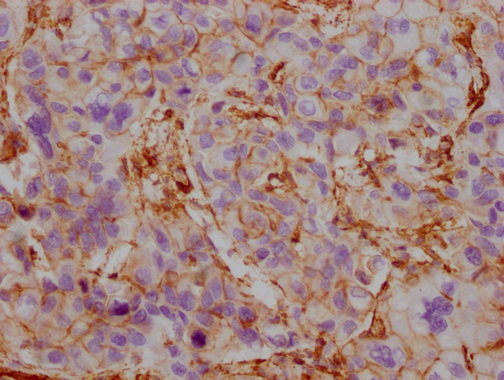

Human liver cancer

1:100